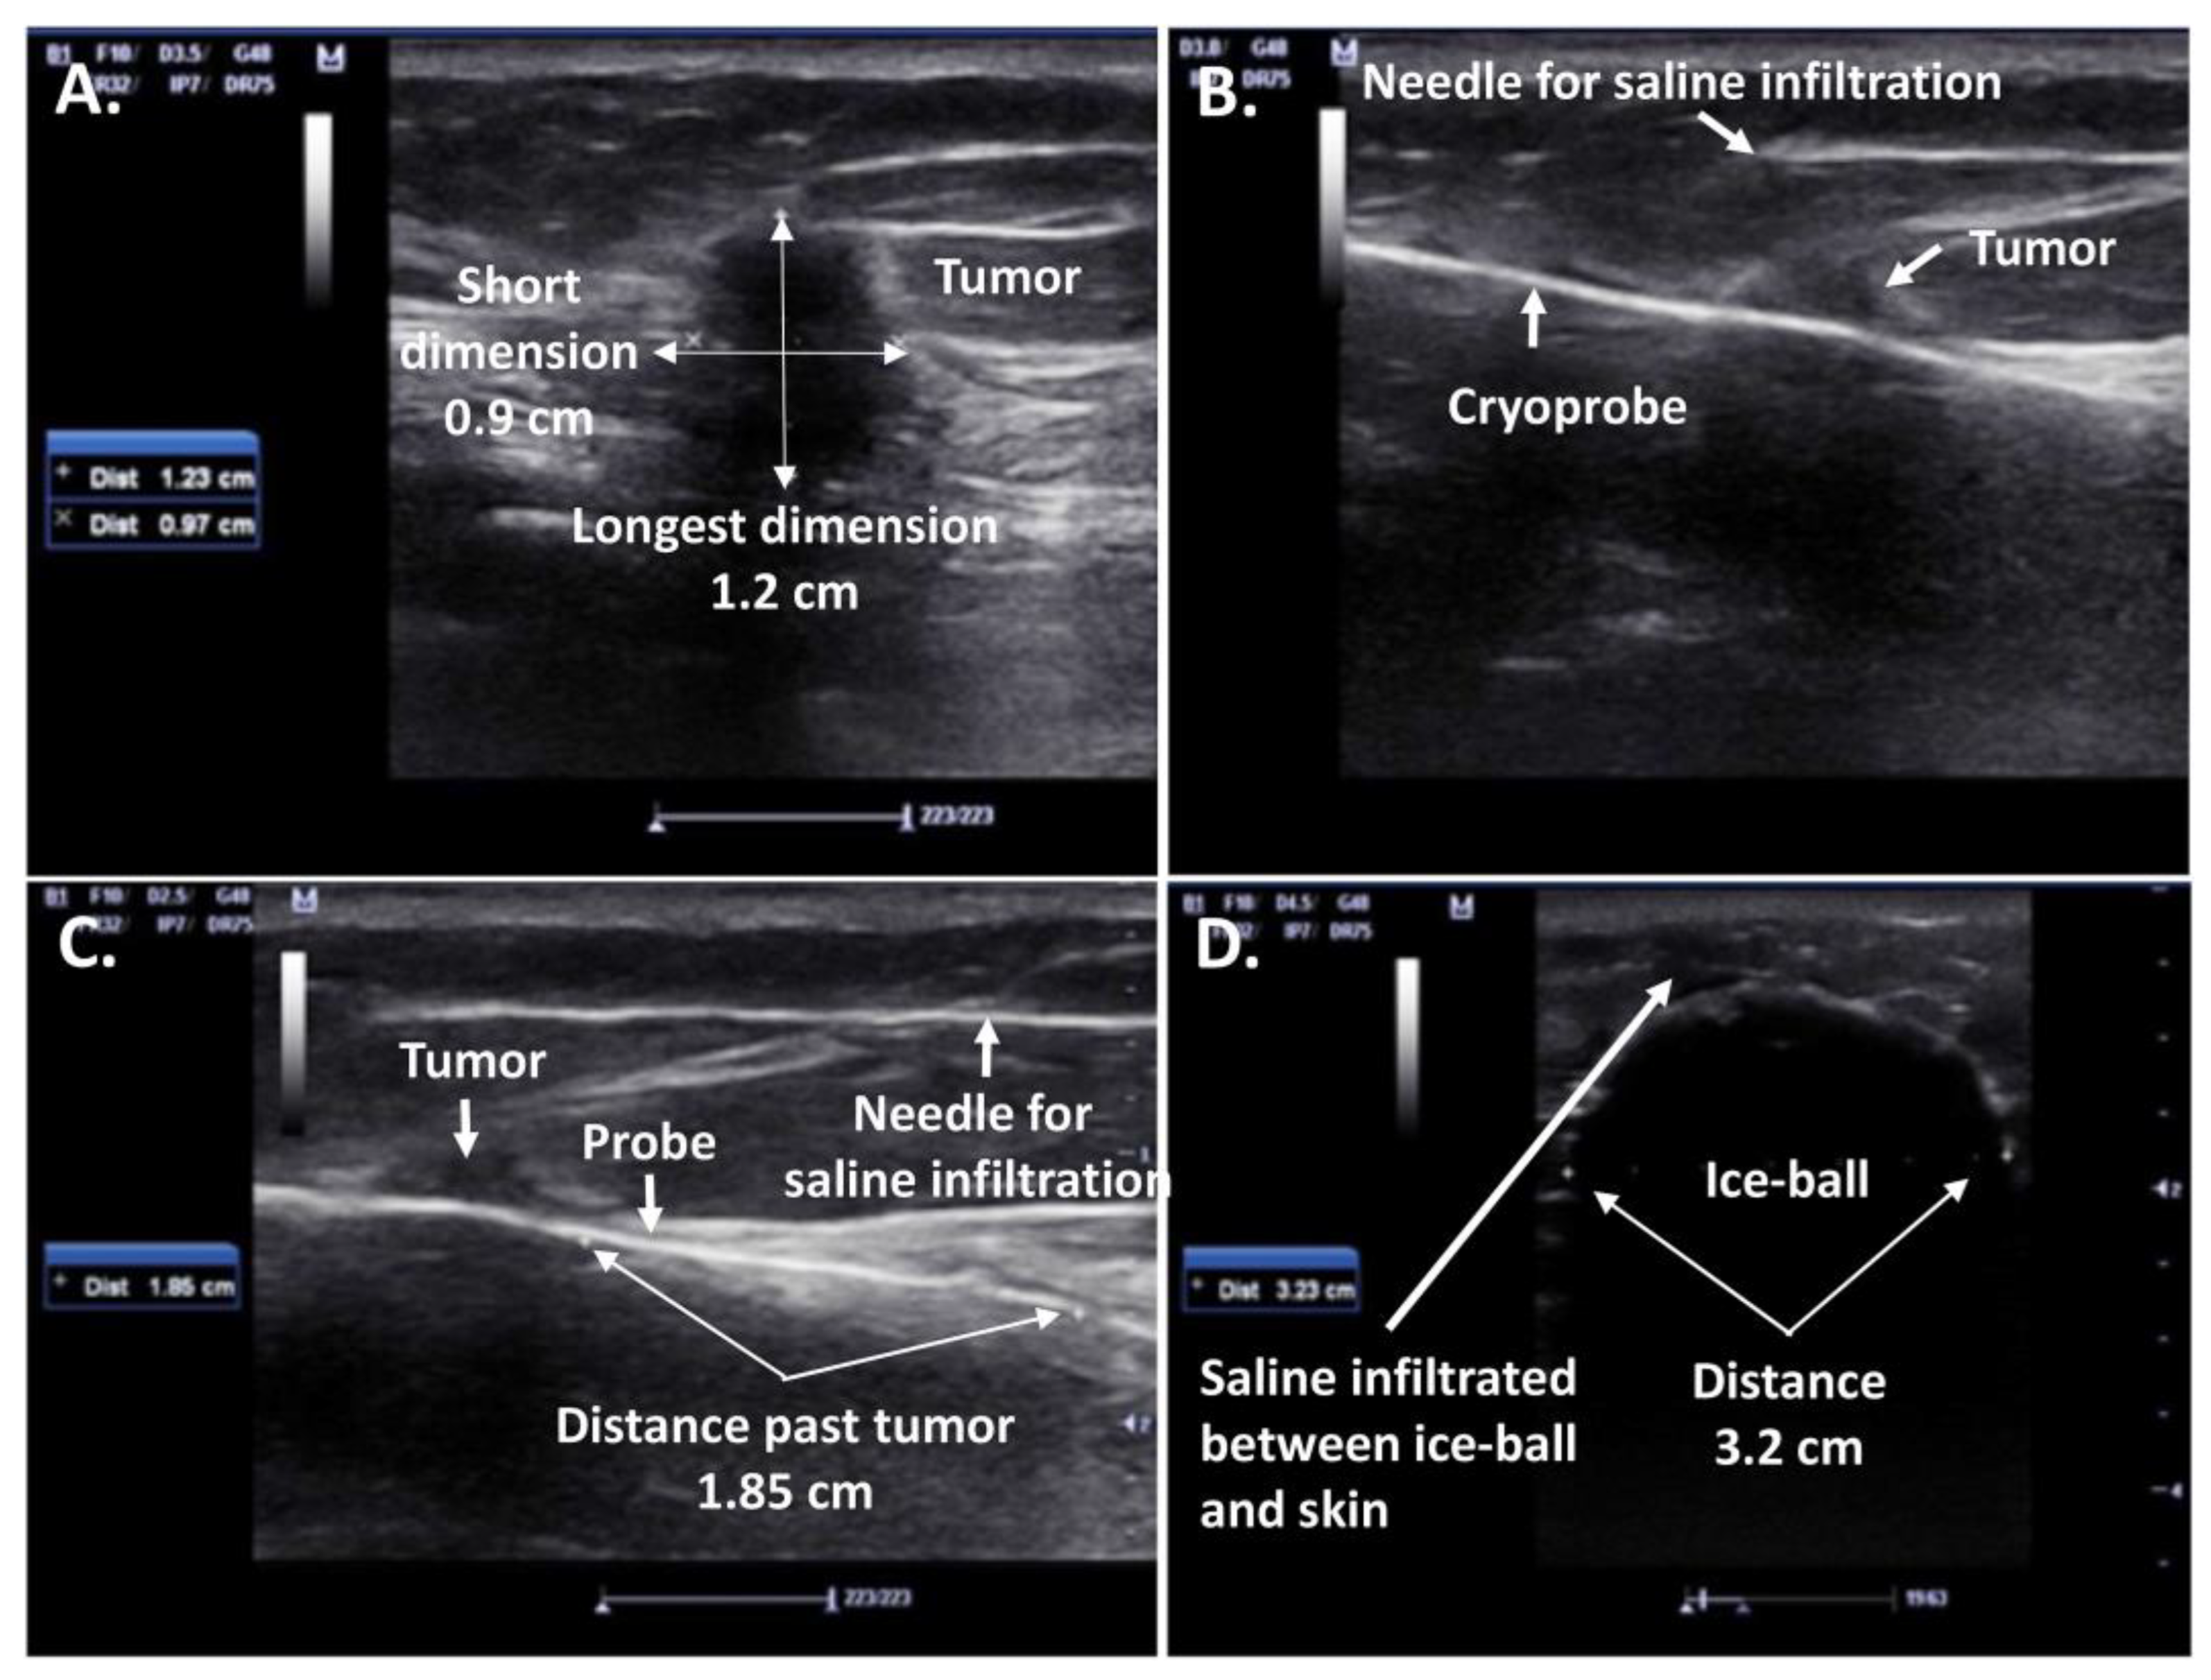

- Ward, R.C.; Lourenco, A.P.; Mainiero, M.B. Ultrasound-Guided Breast Cancer Cryoablation. Am. J. Roentgenol. 2019, 213, 716–722. [Google Scholar] [CrossRef]

- Habrawi, Z.; Melkus, M.W.; Khan, S.; Henderson, J.; Brandi, L.; Chu, V.; Layeequr Rahman, R. Cryoablation: A Promising Non-Operative Therapy for Low-Risk Breast Cancer. Am. J. Surg. 2021, 221, 127–133. [Google Scholar] [CrossRef] [PubMed]

- Littrup, P.J.; Jallad, B.; Chandiwala-Mody, P.; D’Agostini, M.; Adam, B.A.; Bouwman, D. Cryotherapy for Breast Cancer: A Feasibility Study without Excision. J. Vasc. Interv. Radiol. 2009, 20, 1329–1341. [Google Scholar] [CrossRef]